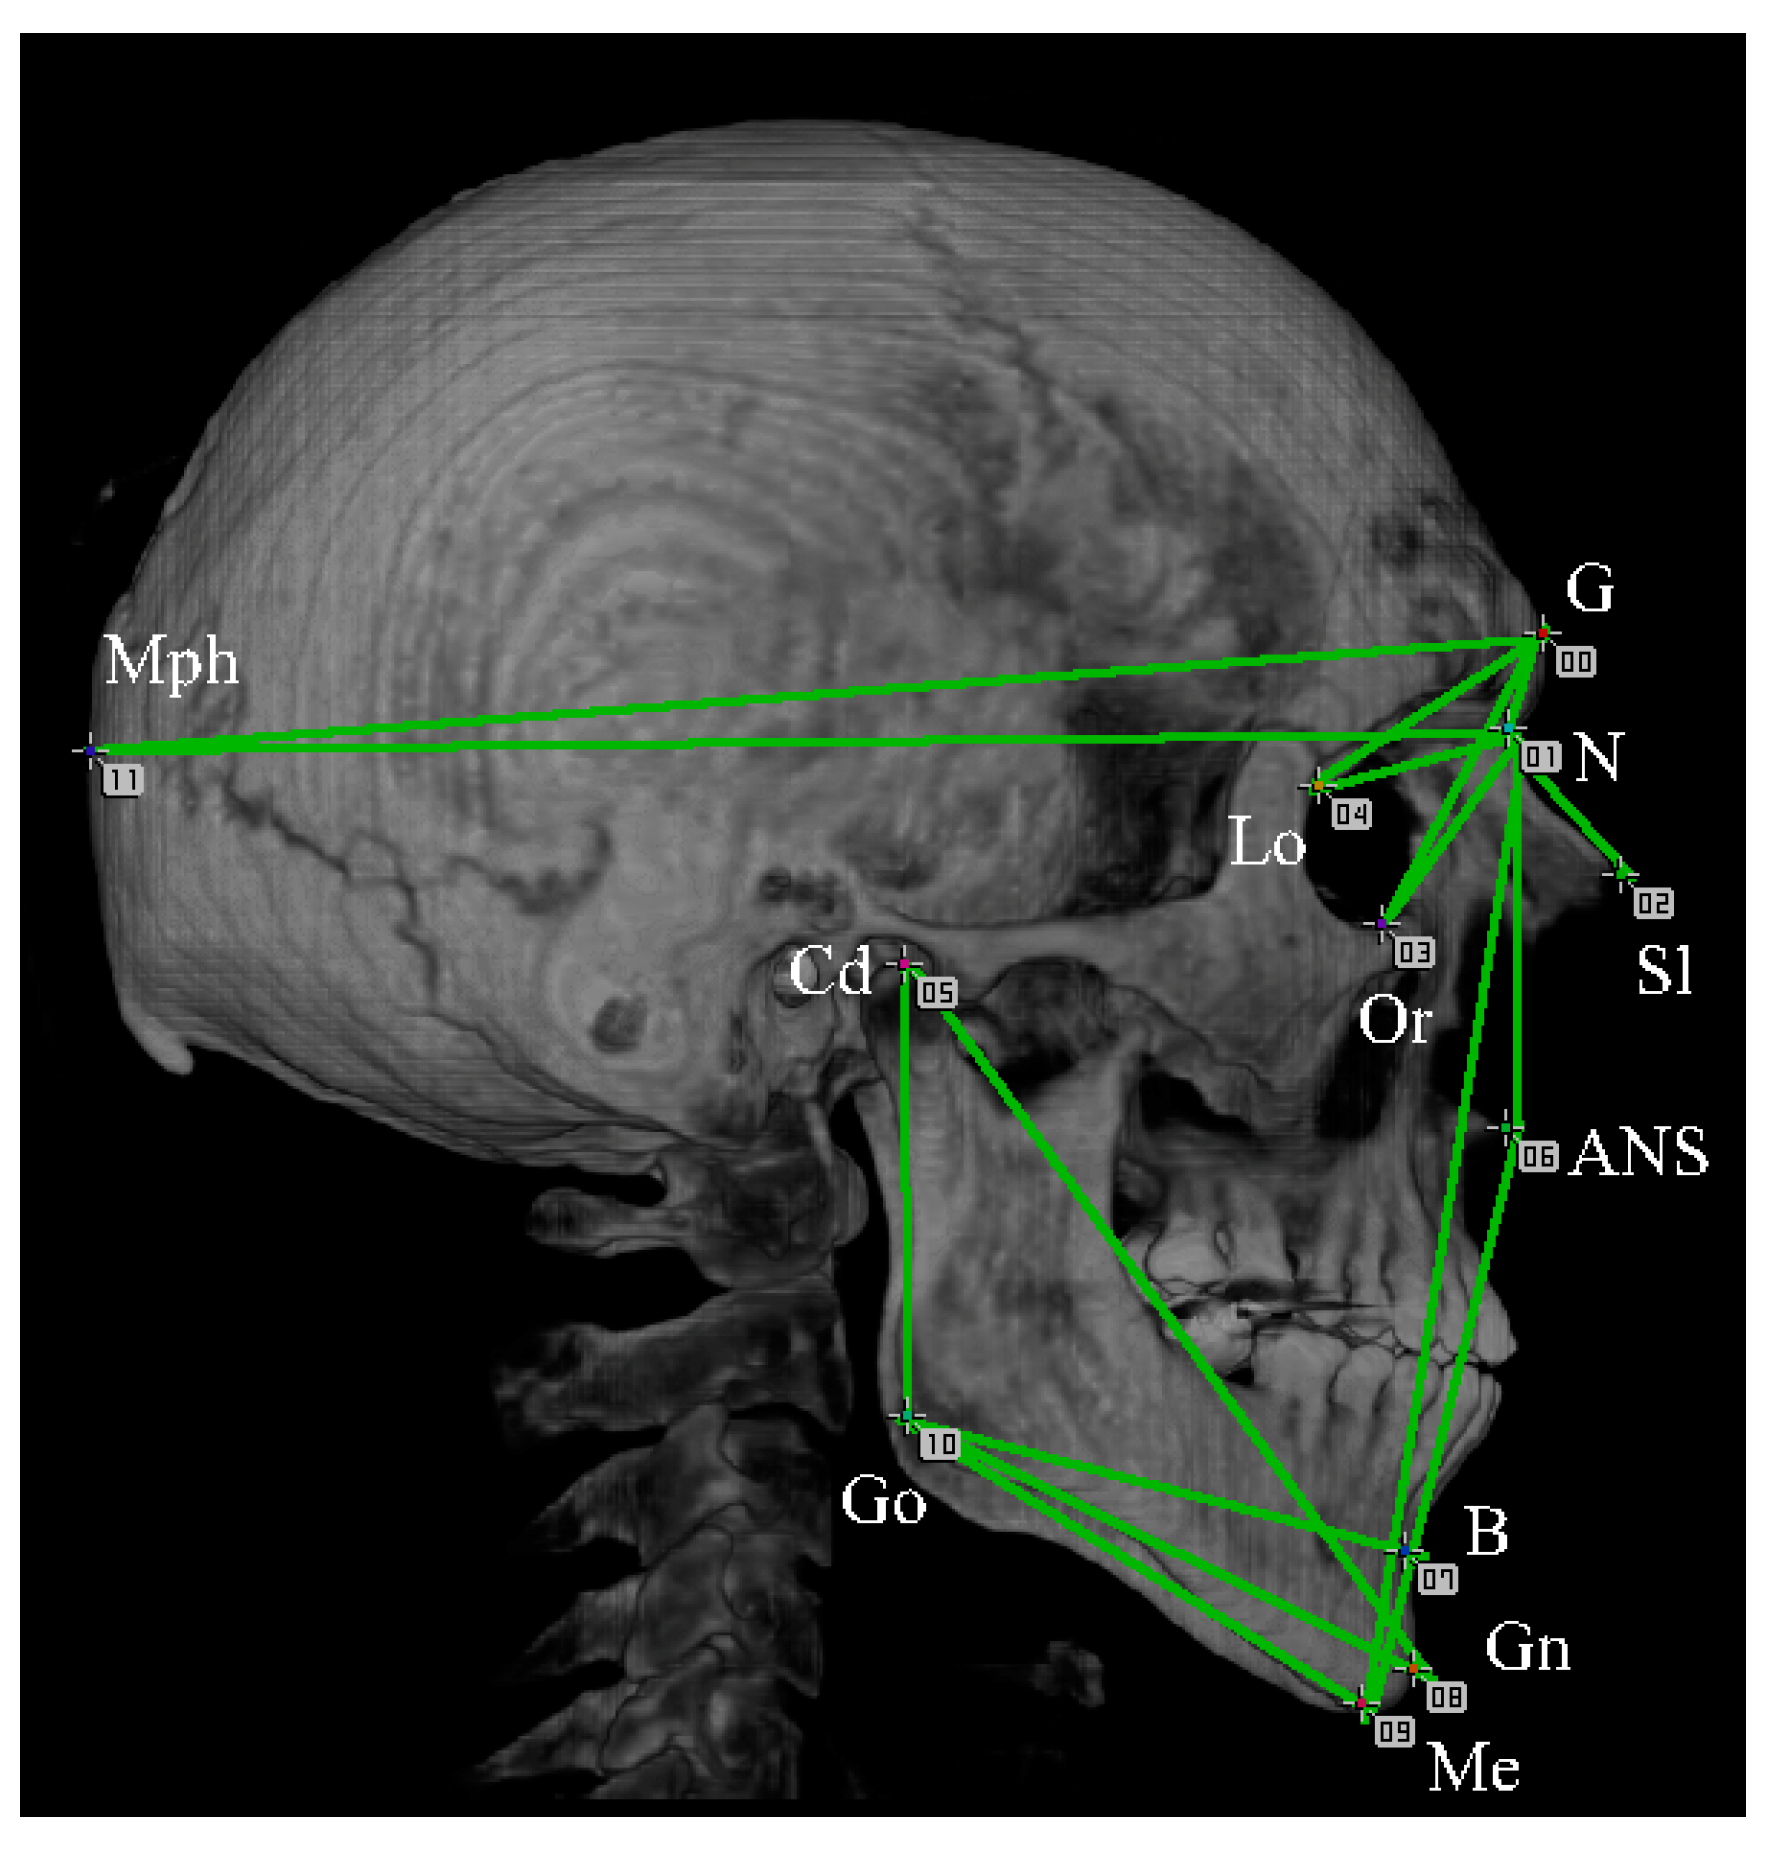

In the lateral template, 12 types of markers (12 markers in total) were used for the measurement (Figure 10). On each lateral measurement, two patterns of templates were created: one viewed from the left side of a cranium and the other viewed from the right side.

Figure 10. Markers and measurement intervals used in anterior images. The measurement intervals are 16 sections indicated by connecting the measurement points with lines. 00: (G) glabella, 01: (N) nasion, 02: (Sl) sellion, 03: (Or) orbitale, 04: (Lo) the oblique orbital line, 05: (Cd) condyle, 06: (ANS) anterior nasal spine, 07: (B) point B, 08: (Gn) gnasion, 09: (Me) menton, 10: (Go) gonion, and 11: (Mph) the most posterior point of head.